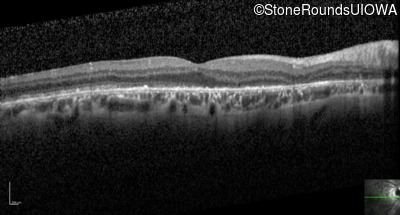

Optical Coherence Tomography - Left - 20/200

Exemplar / OCT Stack